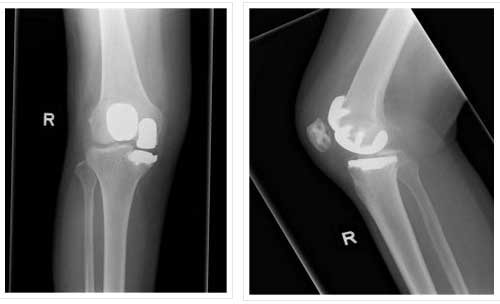

BICOMPARTMENTAL INVOLVEMENT

BICOMPARTMENTAL REPLACEMENT

Bicomp in 55 yr

Bicomp 47yr

BICOMP-POST OP